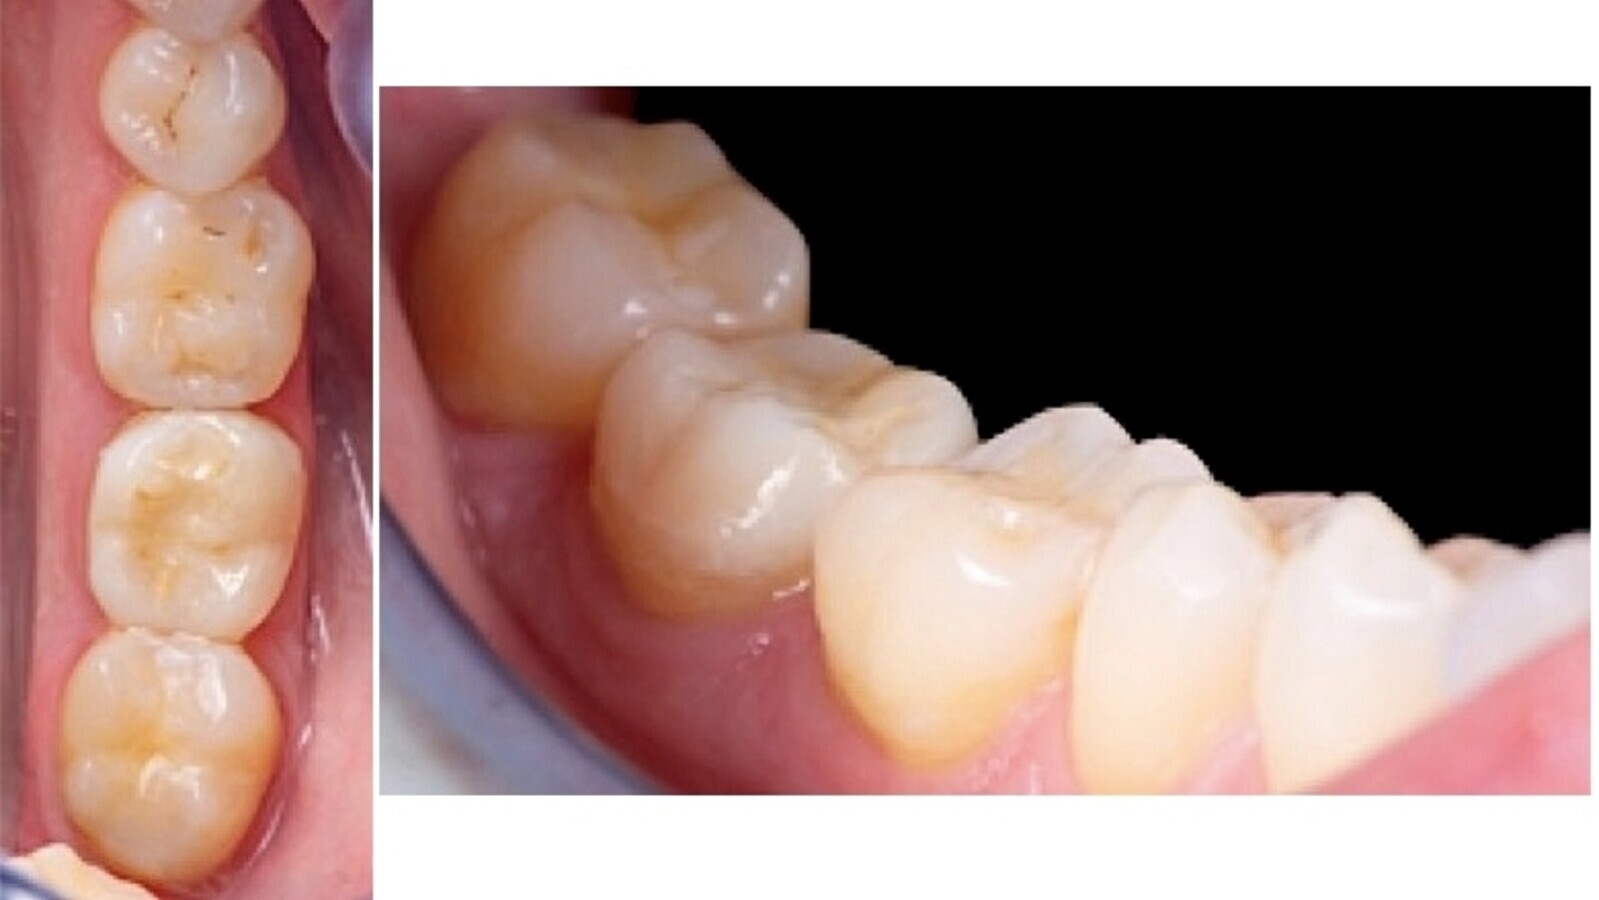

Mujer de 40 años sin ninguna historia médica relevante, acude referida a la clínica del Departamento de Endodoncia y Restauradora de la Universitat Internacional de Catalunya (UIC Barcelona) con dolor muy agudo en la zona inferior derecha de la mandíbula. La paciente fue visitada de urgencia por los estudiantes de pregrado en la Clínica Universitaria Odontológica (CUO) para aliviar el dolor, donde se le diagnosticó una pulpitis irreversible con una periodontitis apical sintomática en el segundo molar inferior derecho (4.7) (Fig. 1).

Fig. 9. Fotografía oclusal y lateral del resultado de la cementación de la incrustación indirecta en 4.7.